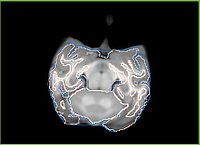

Affine atlas slice

Affine atlas CSF

Affine atlas GM

Affine atlas WM